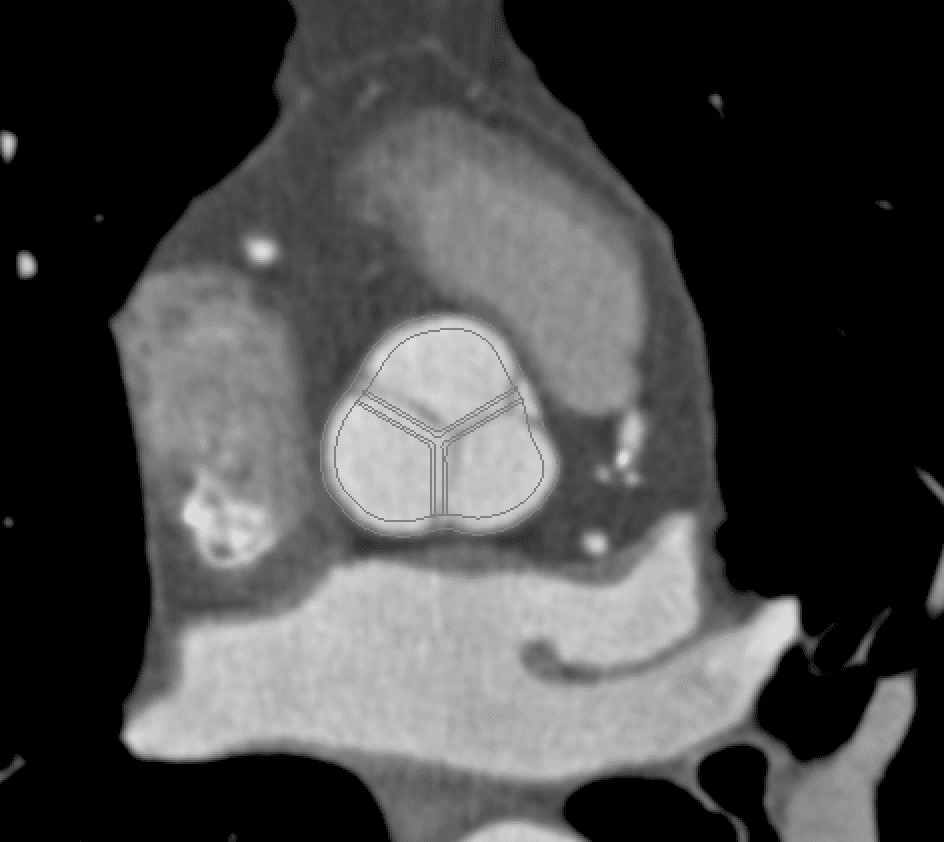

Aortic valve leaflets are thin layered structures that are reinforced by collagen fibers running from commissure to commissure [48, 49, 38]. To obtain geometrical models of the aortic valves, we first constructed idealized aortic valve leaflets with dimensions based on the study of Driessen et al. [38]. We then manually trimmed and morphed the leaflets to fit within the image data. Fig. 3 shows the alignment between the generate model geometry and the image data.

A three-dimensional representation of the aortic root and ascending aorta was generated from publicly available medical image data. This study uses one of the sample data sets from the OsiriX DICOM Image Library that consists of three-dimensional computed tomography angiography (CTA) of an anonymous patient’s chest following administration of a contrast agent. The use of a contrast agent enables better discrimination of the blood vessels and heart chambers than non-contrast CT images. The image data were acquired at the Ronald Reagan University of California at Los Angeles Medical Center in Santa Monica, CA using a Siemens SOMATOM Sensation 16 CT scanner. The image resolution is 512512355 with a voxel size of 0.470.470.5 mm. The image was processed by an anisotropic diffusion filter to mitigate noise. Sample renderings of the patient data are shown in Fig. 1.